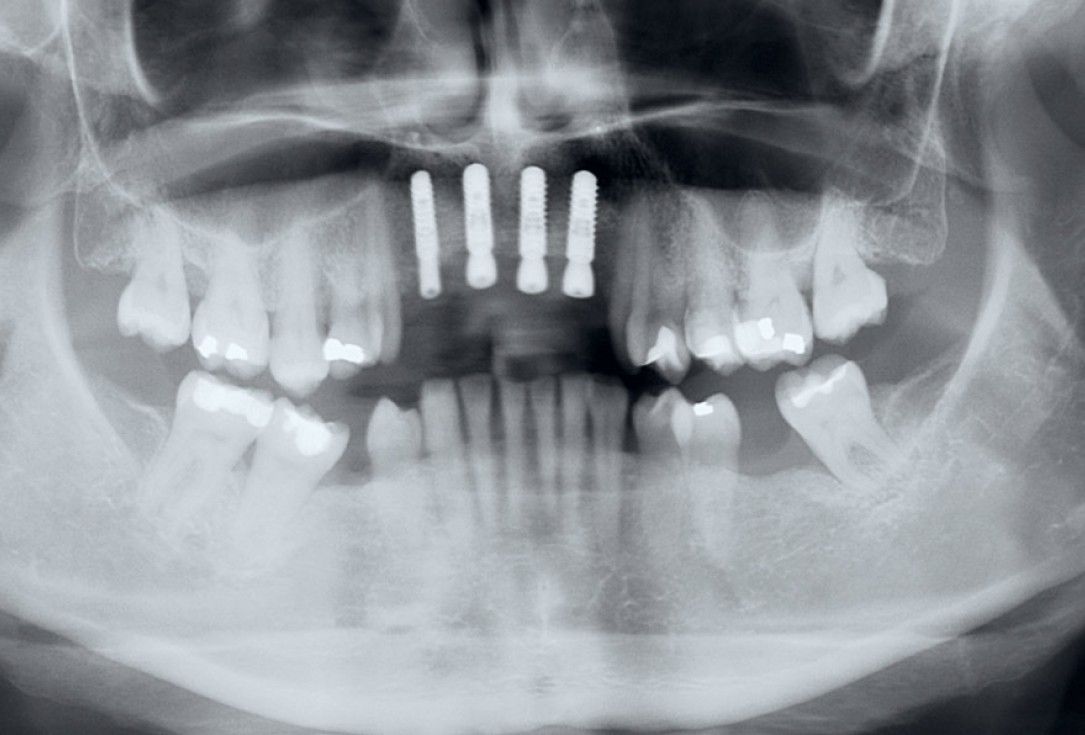

2/17 - Pre-operative x-ray scan: severe bone loss around three failing implantsRestoration of all four incisors with maxgraft® bonebuilder - Dr. Dr. Dr. O. Blume